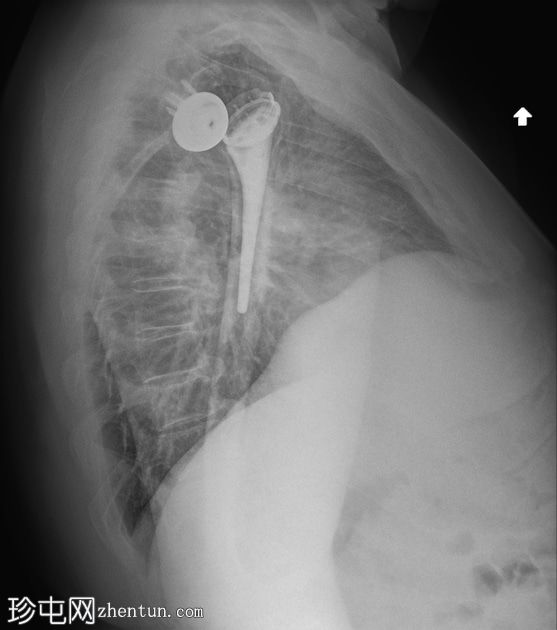

正面 - 内旋

全肩关节置换术后肱骨假体前脱位,伴假体分离。